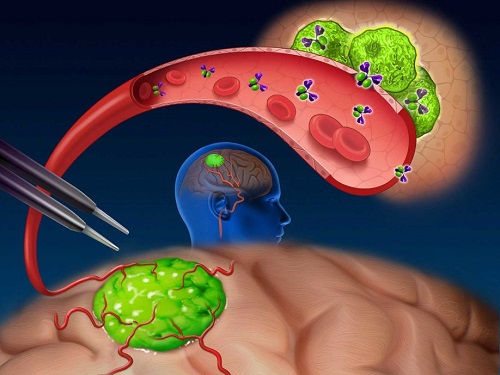

Patients with glioma often undergo surgical procedures to reduce or remove their cancer. Doctors who perform this type of surgery are well‑trained in removing all the cancer that can be seen during your operation. However, there are times when the tumor looks like normal brain tissue or there are cancer deposits that are too small to be seen by the surgeon.

We hope to show that panitumumab-IRDye800, an imaging agent, is safe to use in brain cancer patients. We will also evaluate if panitumumab-IRDye800 can help surgeons to better distinguish cancer cells from normal brain tissue and identify small cancer lesions that cannot be seen using current imaging methods.

Panitumumab‑IRDye800 is an investigational imaging agent that contains a dye molecule that surgeons and researchers can image using light waves both during surgery and after the surgery on removed tissues.

Near-infrared (NIR) labeled EGFR antibody, panitumumab-IRDye800, is systemically infused in high-grade glioma patients and specifically binds to tumor cells across the blood-brain barrier to improve intraoperative visualization during MRI-guided resection.